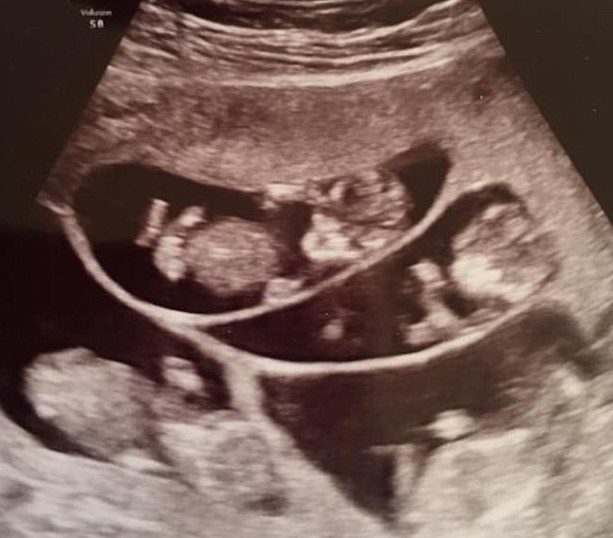

As the days counted down to the monumental birth of their septuplets, Bobbi and Kenny McCaughey were filled with a whirlwind of emotions. It was only natural for anxiety to creep in during such an extraordinary and high-risk situation. The couple was well aware of the medical challenges and potential complications associated with delivering seven babies at once. They had spent months preparing themselves mentally and emotionally, yet the uncertainty of what lay ahead still weighed heavily on their minds.

There were moments when the enormity of their decision and the risks involved gave rise to nervousness and doubt. Questions lingered in their hearts: Would the babies be healthy? Would Bobbi’s body endure the strain of such a rare and demanding birth? How would they manage to care for seven newborns at once? These thoughts occasionally left them feeling overwhelmed, but they never allowed fear to overshadow their determination.